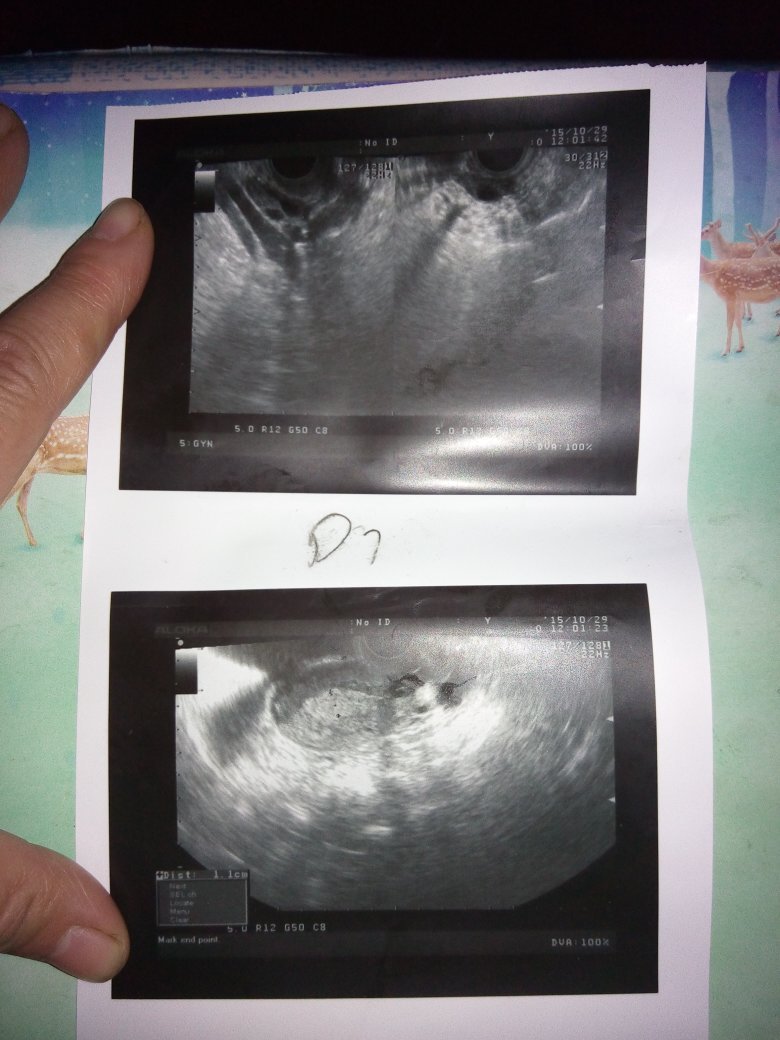

有懂得帮我看一下吗 在沈阳医大二院做的不孕检查 这个是月经第七天的检查结果 麻烦有明白的亲帮一下忙

有懂得帮我看一下吗 在沈阳医大二院做的不孕检查 这个是月经第七天的检查结果 麻烦有明白的亲帮一下忙 跪谢